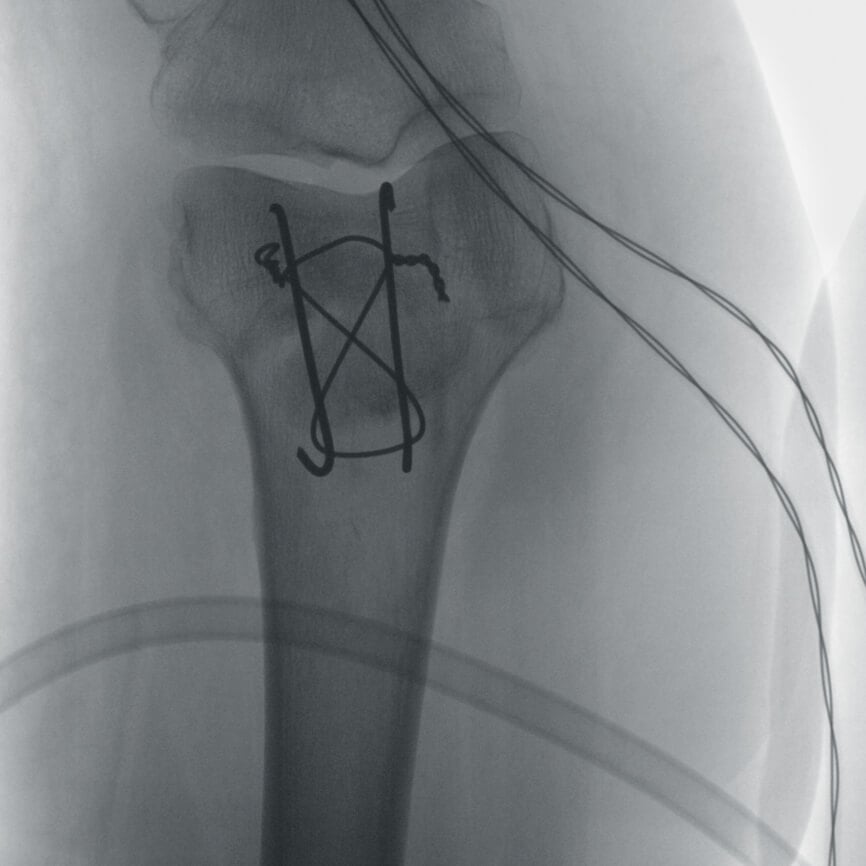

Orthopedic and trauma surgery are part of the clinical routine. From a pelvic ring fracture and stabilizing the sacroiliac joint to treating the calcaneus, intraoperative imaging using a mobile C-arm is the gold standard in the treatment of complex fractures.

Ziehm Imaging offers not only excellent 2D imaging but also leading

3D imaging. The portfolio offers maximum flexibility thanks to various detector and individual 3D volume sizes.

The combination of a powerful generator and CMOS flat-panel technology enables significantly more distinguishable anatomies, defined bone crests, and optimum slice views without disruptive artifacts – even with obese patients.